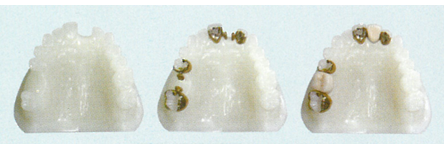

※写真撮影技術が未熟なため、セット前の模型上の写真を掲載します。

●セット前の様子(頬側から)

●セット後の様子(頬側から)

●セット後の様子(舌側から)